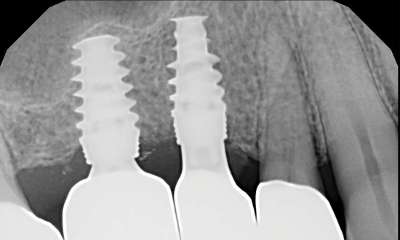

Anchor tooth for the patient's bridge failed and had to be extracted. Patient had two implants placed rather than replacing with a longer-spanning bridge.